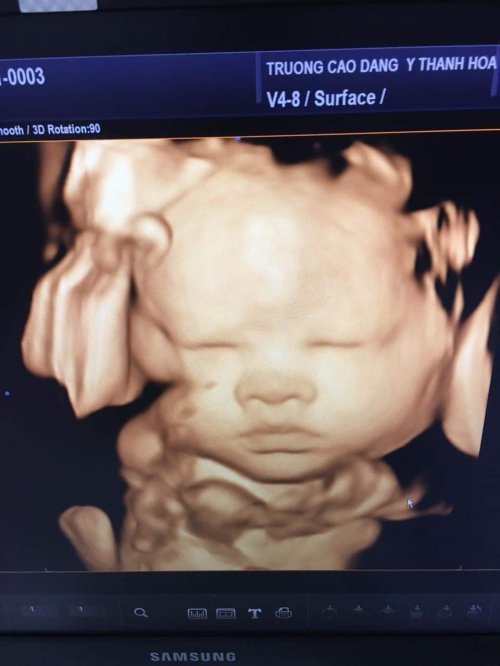

Khi mang thai, siêu âm cho nhiều giá trị chẩn đoán và giúp phát hiện những bất thường trong quá trình mang thai. Thông thường trong mỗi lần mang thai, tối thiểu sản phụ cần siêu âm 3 lần vào các mốc sau: 11-14 tuần, 18-22 tuần và 30 - 32 tuần.

- Siêu âm thai định kỳ là việc làm rất cần thiết để theo dõi quá trình mang thai và kịp thời phát hiện được các bệnh tiềm ẩn của thai nhi cũng như thai phụ. Siêu âm là phương tiện chuẩn đoán hình ảnh giúp đánh giá sức khỏe của phụ nữ mang thai. Đây cũng là một kỹ thuật an toàn, chính xác và đơn giản.

Tại Phòng khám đa khoa Cao đẳng Y tế Thanh Hoá quy tụđội ngũ y, bác sĩ giàu kinh nghiệm, trình độ chuyên môn cao. Cùng sự hỗ trợđắc lực của hệ thống trang thiết bị y tế hiện đại, đặc biệt là hệ thống máy siêu âm Accuvic A30 và máy siêu âm Volusun P8 sẽ giúp tầm soát dị tật thai nhi một cách hiệu quả nhất như: tim bẩm sinh, hội chứng DOWN...Ngoài ra phòng khám còn triển khai làm các xét nghiệm như: NIPT, DOUBLE test, TRIPLE test, tiểu đường.....